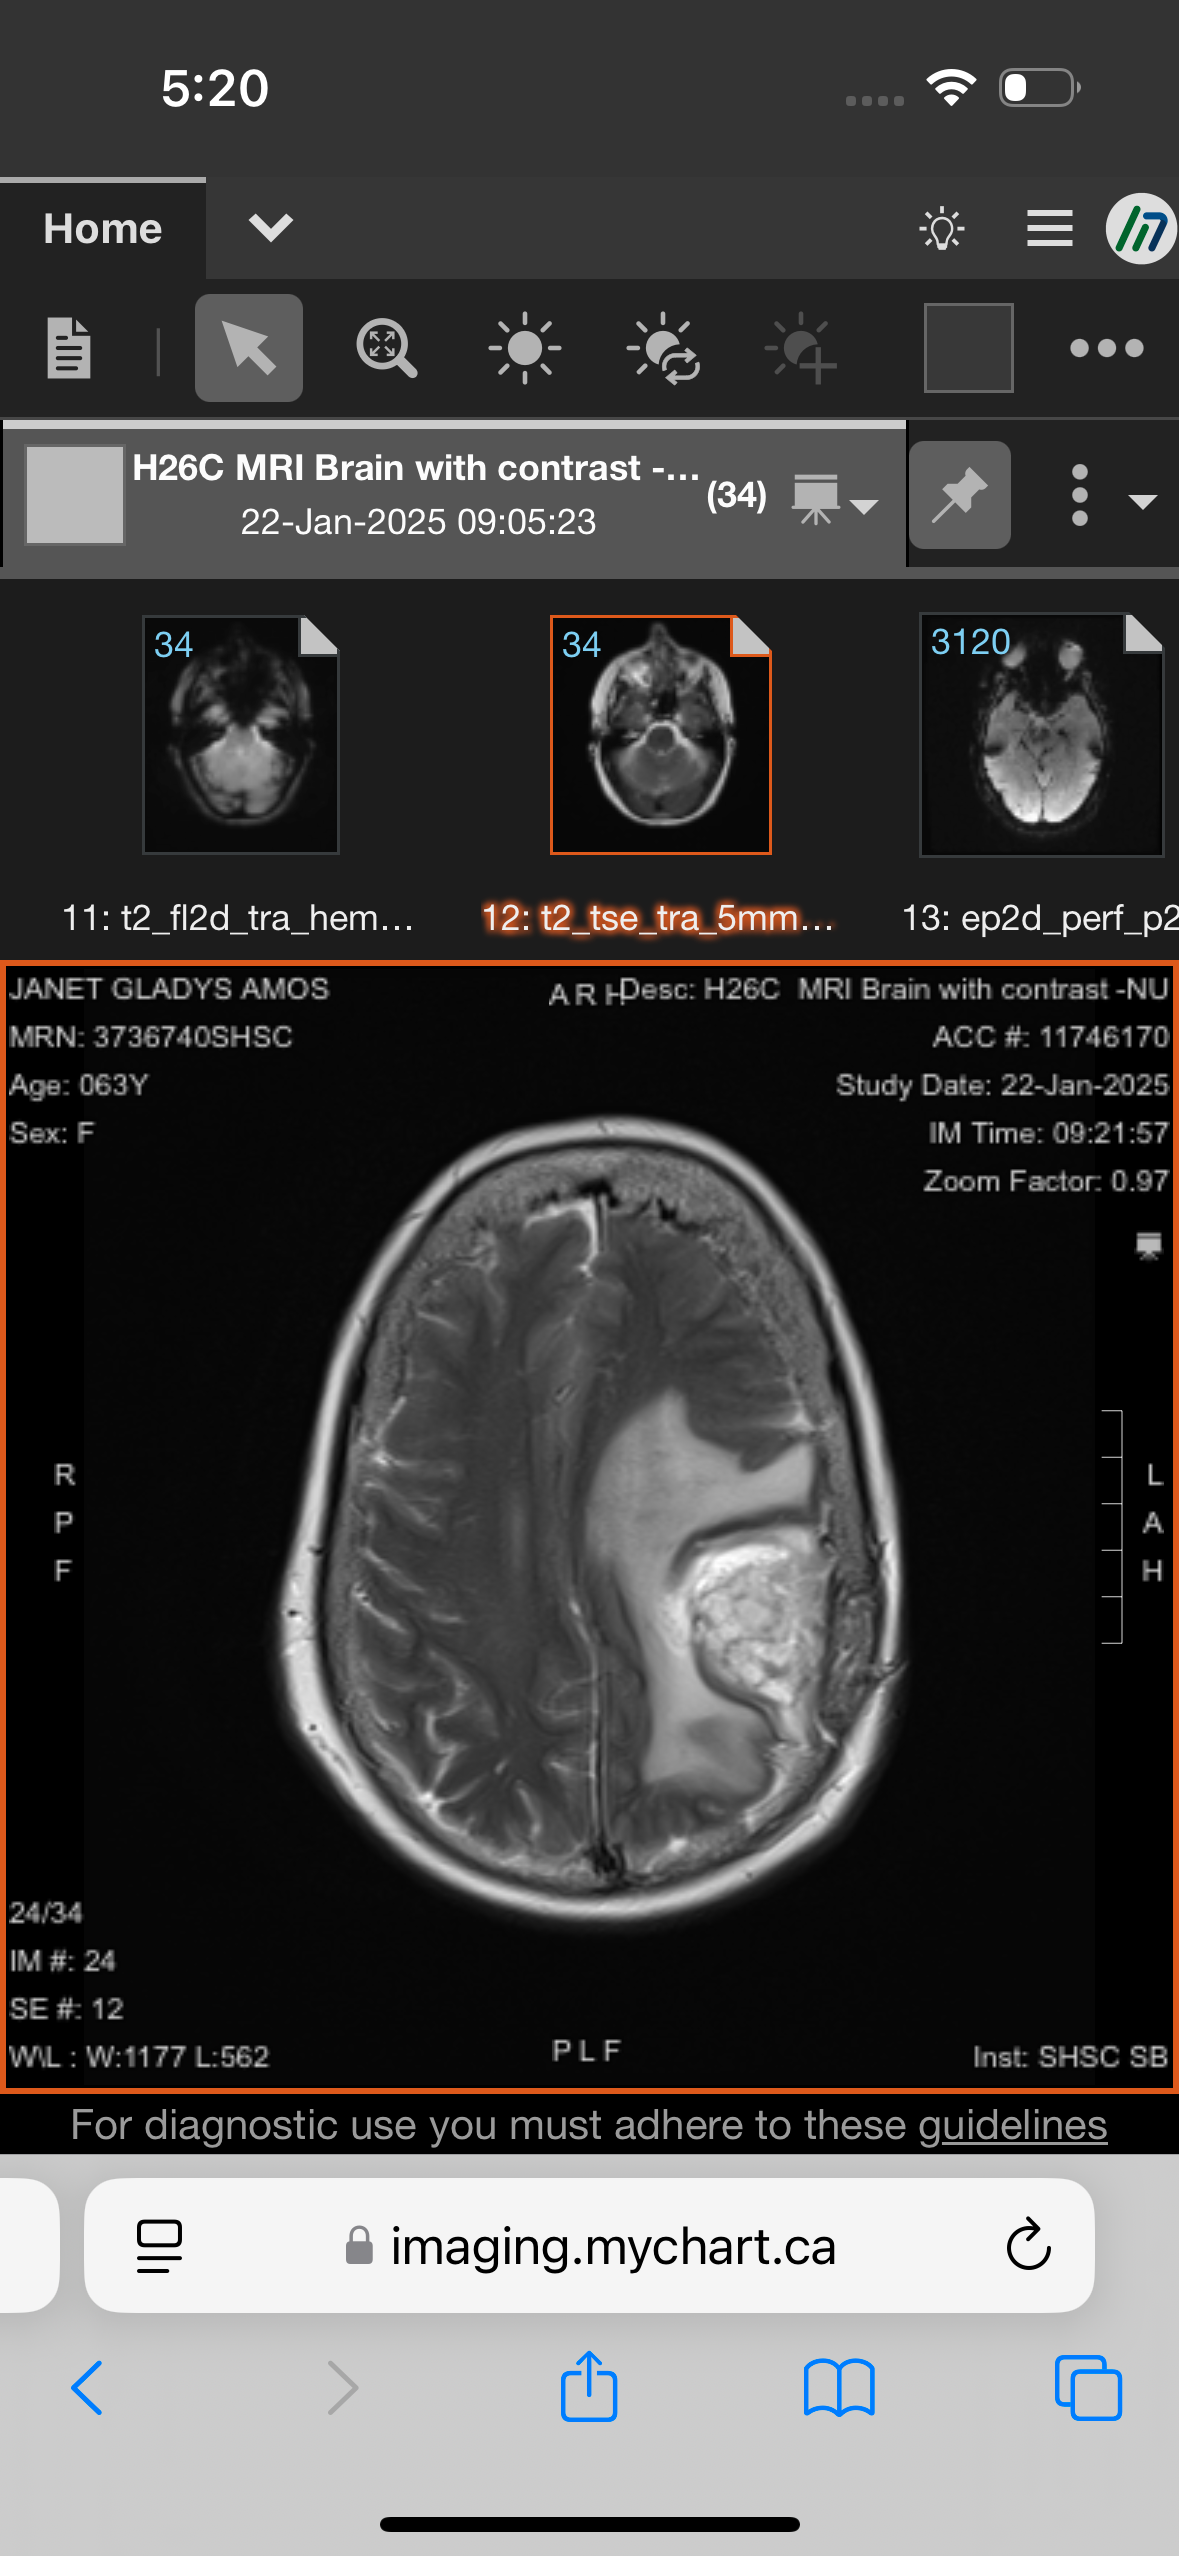

In October 2024, my mom was diagnosed with glioblastoma, an aggressive form of brain cancer. She bravely completed standard treatment (radiation and chemotherapy) by December 19, 2024. Despite her strength, her condition has progressed—she has lost much of her speech and mobility on the right side and now requires around-the-clock care.